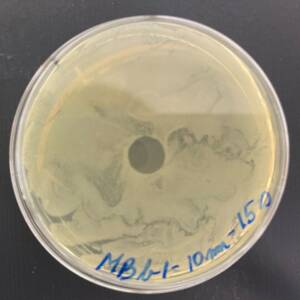

Treatment of the Petri plates inoculated with live bacteria using Ocu-Vet UV-C for 15 seconds at a 10 mm distance.

Photo of the Petri plate, 72 hours after bacterial (Moraxella bovis) inoculation. The image shows complete (positive) bacterial growth inhibition (full translucency) at the treatment site after one dose of UV-C for 15 seconds at a 10 mm distance.